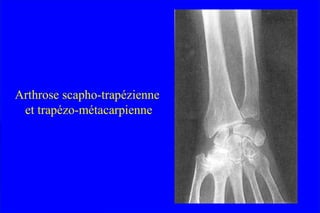

RhizarthroseRhizarthrose

 EssentiellementEssentiellement ffééminimeminime

 Le plus souvent bilatLe plus souvent bilatééralerale

 Douleur mDouleur méécanique de la base du pouce au bordcanique de la base du pouce au bord

radial de la mainradial de la main

 Douleur lancinante,Douleur lancinante, éévolution par poussvolution par poussééeses

 Manque de force, lâchage des objets, difficultManque de force, lâchage des objets, difficultéé dede

prprééhensionhension

 DouleurDouleur àà la pression de lla pression de l’’interligneinterligne articulairearticulaire

 DDééformation de lformation de l’’articulation :articulation :

adduction du 1er madduction du 1er méétacarpien,tacarpien, hyperextensionhyperextension

rrééactionnelle de lactionnelle de l’’art MP, etart MP, et flessumflessum de lde l’’art IPart IP

 Aspect de pouce en ZAspect de pouce en Z

Arthrose scapho-trapézienne

et trapézo-métacarpienne